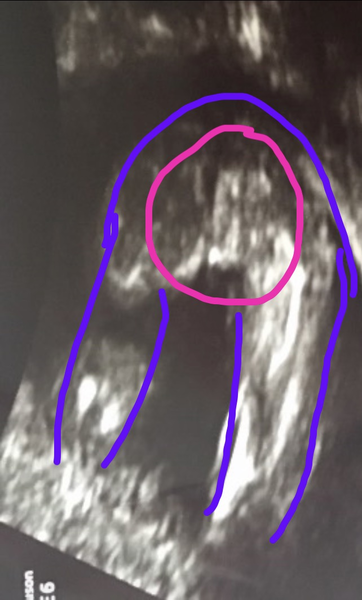

user1480264544 · 14/07/2017 16:42

So I've drawn the legs and bum outline in purple and circled the bits in pink, to be fair a few people have told me they can't see clearly but I've spent way to long thinking she's a girl lol I can't see a pair of balls so that's good enough for me lol x

Oh I can see it now @user1480264544 😂😂

Now I'm not so sure it was balls I saw on my scan! 😂😂